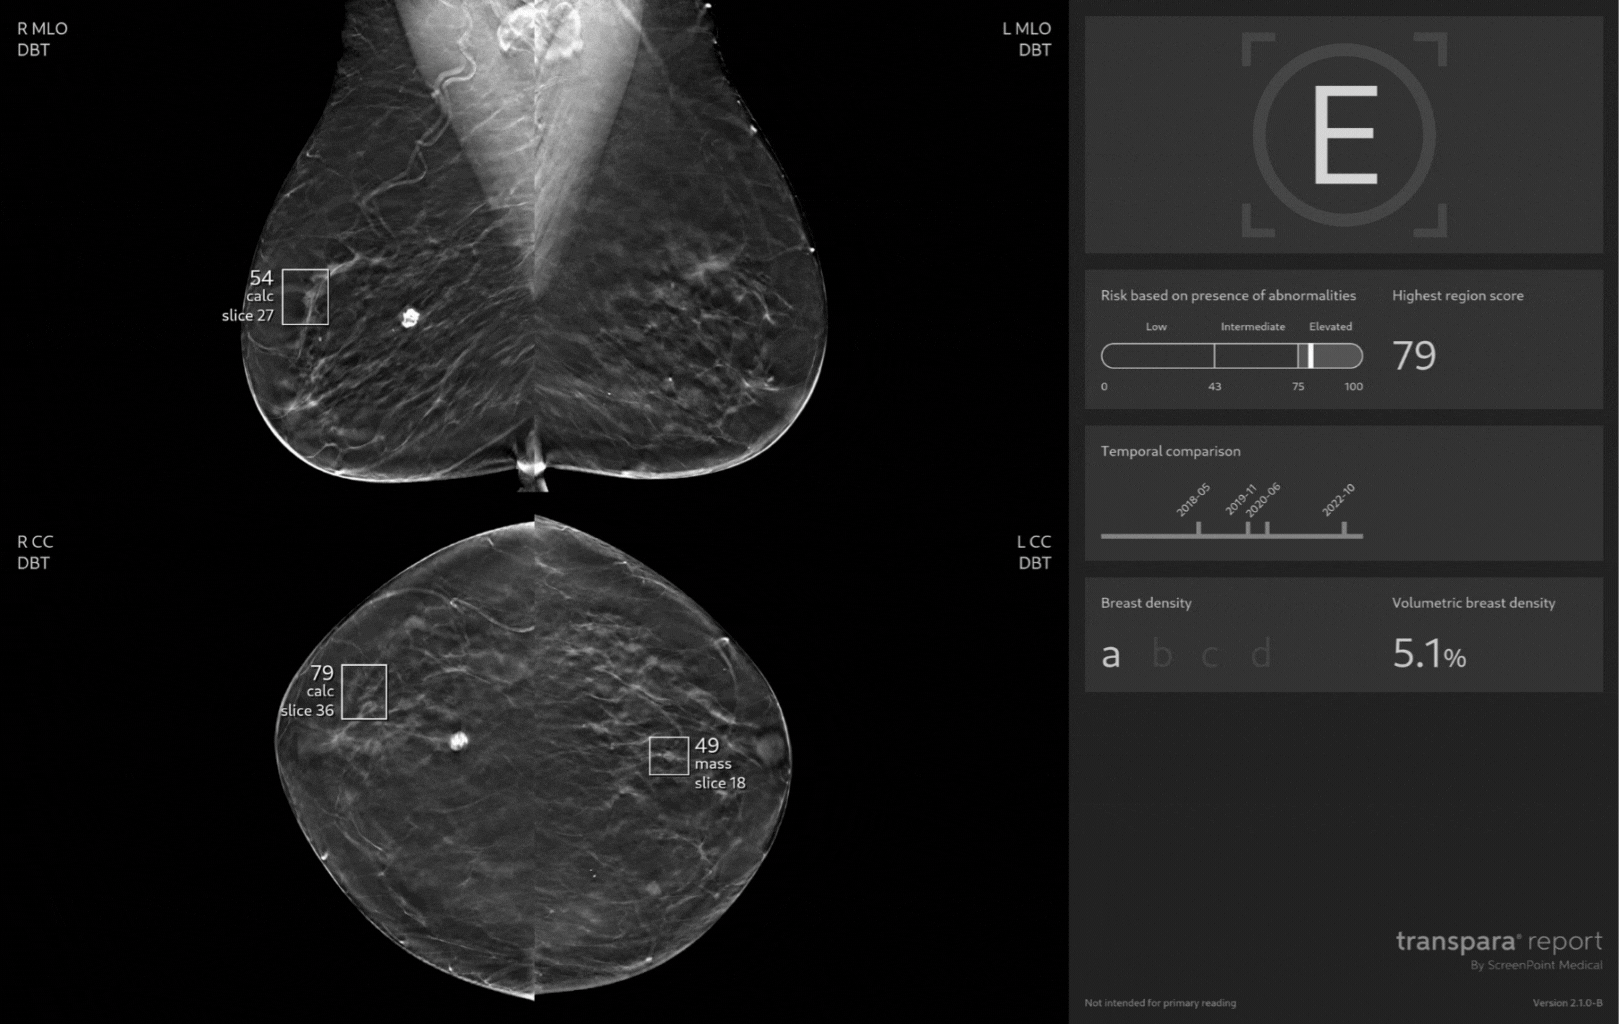

The Transpara Report

Transpara Detection categorizes exams based on their risk of breast cancer being present using three categories of risk - Elevated, Intermediate, Low -, alongside Region Risk marks which highlight areas of suspicion.

Unique to Transpara Detection, Low Risk category cases are unmarked for expedited review, with an NPV of 99.97% underscoring your confidence to quickly review these exams.

Transpara Density combines a BI-RADS-like assessment as well as volumetric breast density for consistency in analysis and reporting.

The power of priors in action: track findings across up to three prior mammograms (if available), from 9 months to 6.5 years prior.